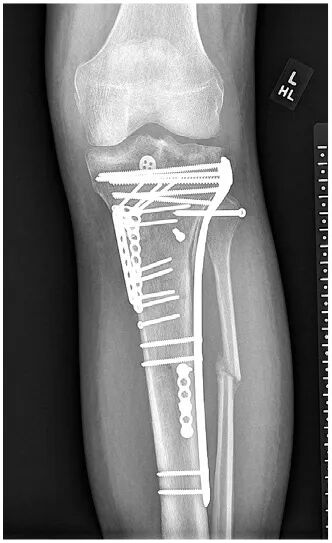

Intraoperative fluoroscopy radiographs showed near anatomic restoration of the bony anatomy (Fig. 4). Multiple minifragment plates and independent lag screws were used for fragment-specific fixation and provisional reduction control. The proximal tibial locking plate was used after fragment-specific fixation in neutralization mode for definitive fixation. The bony PCL avulsion fragment, including the insertion of the posterior horn of the lateral meniscus, was repaired using proximal and distal button fixation bridged with SutureTape. This was accomplished via the posteromedial approach utilized for bony fixation that was extended intracapsularly. An iatrogenic ramp lesion (meniscocapsular separation) was created to improve exposure, and this was repaired primarily upon closure. The fibula was reduced and secured with a screw.

Figure 4: Intraoperative AP fluoroscopic radiograph shows near anatomic reduction.